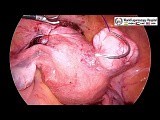

Live - Gebarmutter Entfernung

Entfernen Operation - Myom

Entfernen Op - Myome